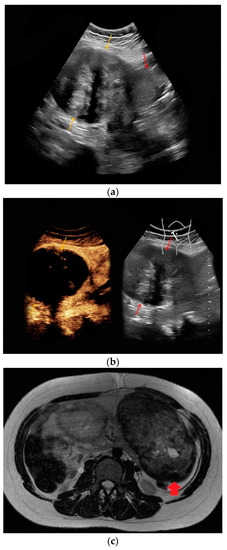

| #1 | 30 | 27 | Renal angiomyolipoma | B-mode: hypoechoic, 14 cm Doppler: no hypervascularization CEUS: rapid early contrast enhancement, slight late wash-out | T1-hypointense, T2-hypointense, restricted diffusion |